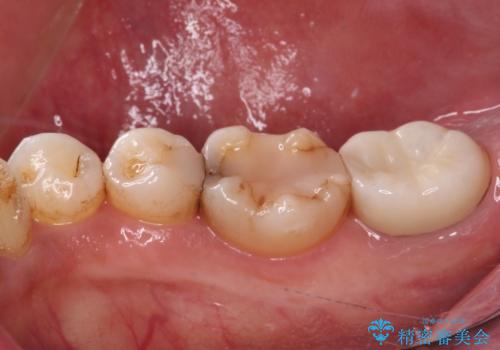

- かかりつけ医にて、歯の高さが不足しているためセラミッククラウンの装着はできないと言われたとのことで来院された患者様です。

診察したところ、確かに歯の高さは不足していましたが、土台の立て直しや歯の削り方を調整することでオールセラミッククラウンでも補綴可能と思われました。

ただし、クラウンの厚みは極力薄くした方が維持力が増すため、高強度のフルジルコニアクラウンにて補綴治療することとしました。

仮歯が途中外れることもなく、無事に補綴治療を行うことができました。

歯石や磨き残しなどが多いため、今後クリーニングを行っていきます。